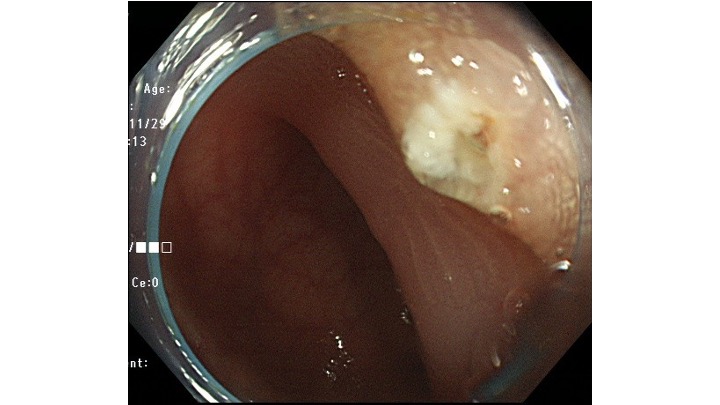

意外と基部は狭く、切除面積は少なくすみました。

後出血予防にCLIPをしています。